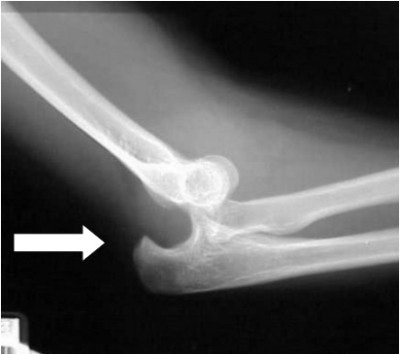

In figure 1 we have an attempted AP view of the elbow in a 10-year-old male. Because the child was unable to fully extend his arm, his body was partially oblique to the affected side, and the arm was extended as far as possible.

Upon completion of the lateral film (figure 2), which was done with the film tucked between the child's arm and his body and shot cross-table in a wheelchair, it is evident why the arm is in a fixed position. Note the subluxation of the humeral condyles from the olecranon process (arrow).